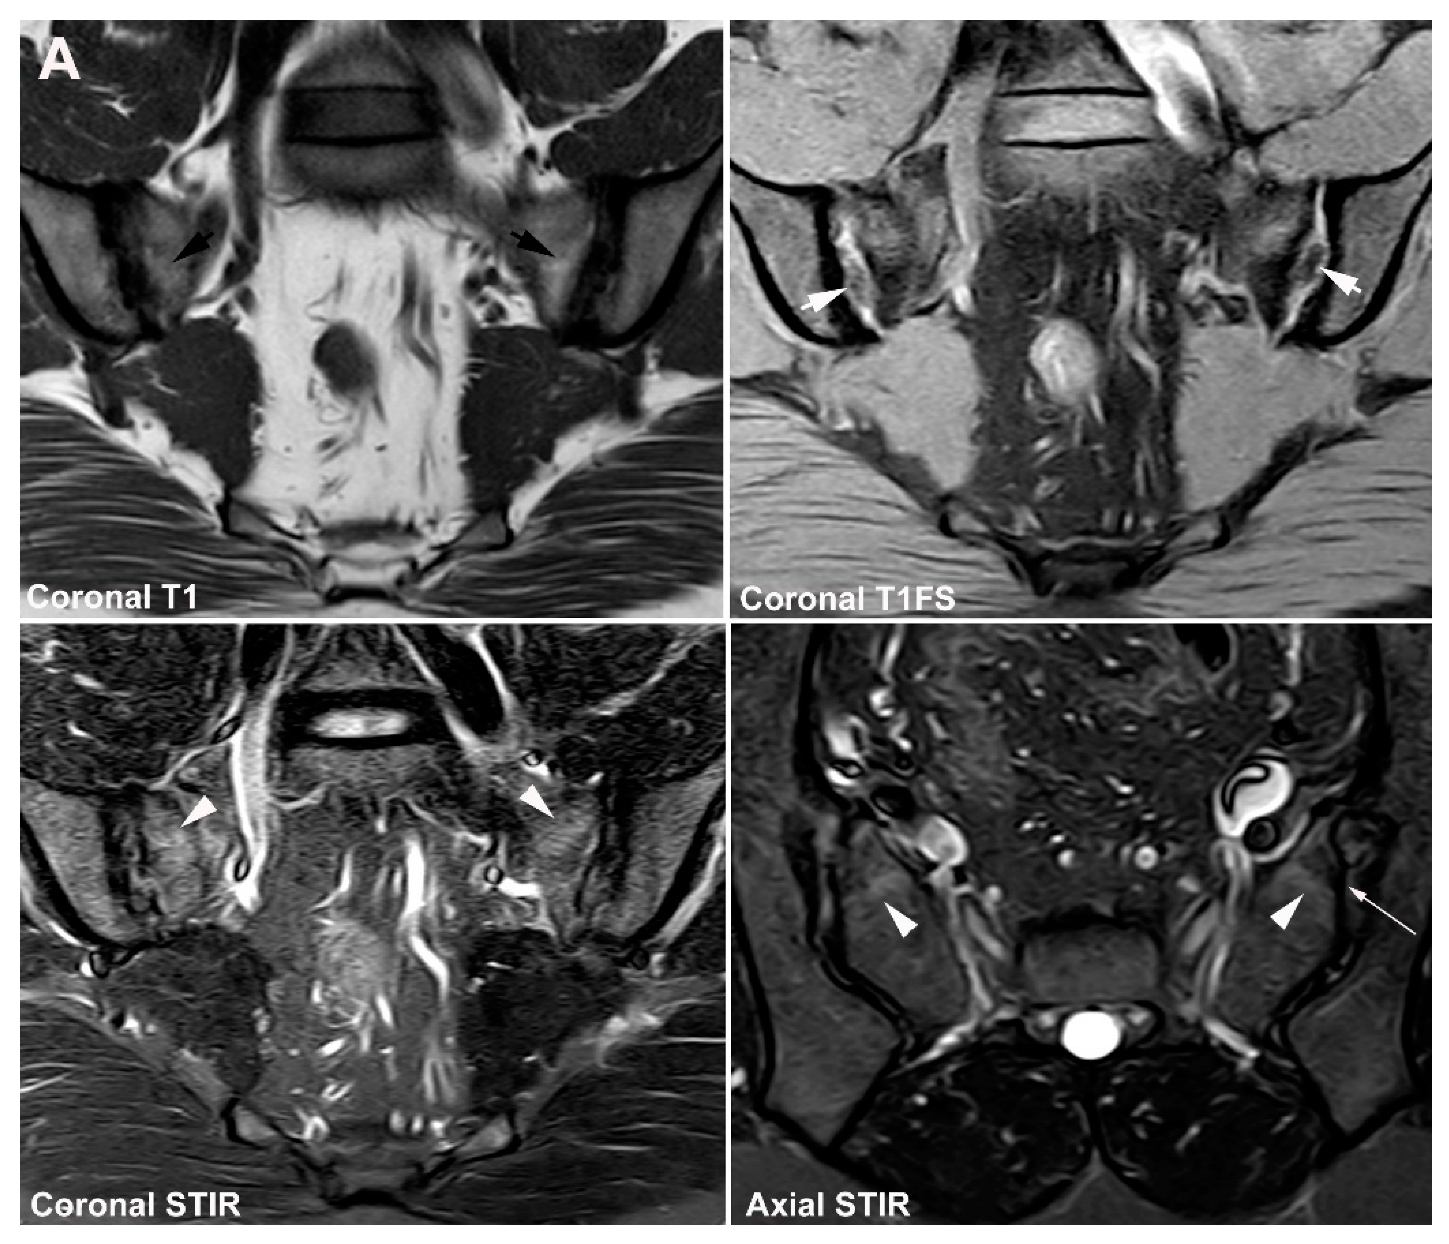

5.1. Osteitis Condensans ilii (OCI)

5.2. Pregnancy-Related Changes